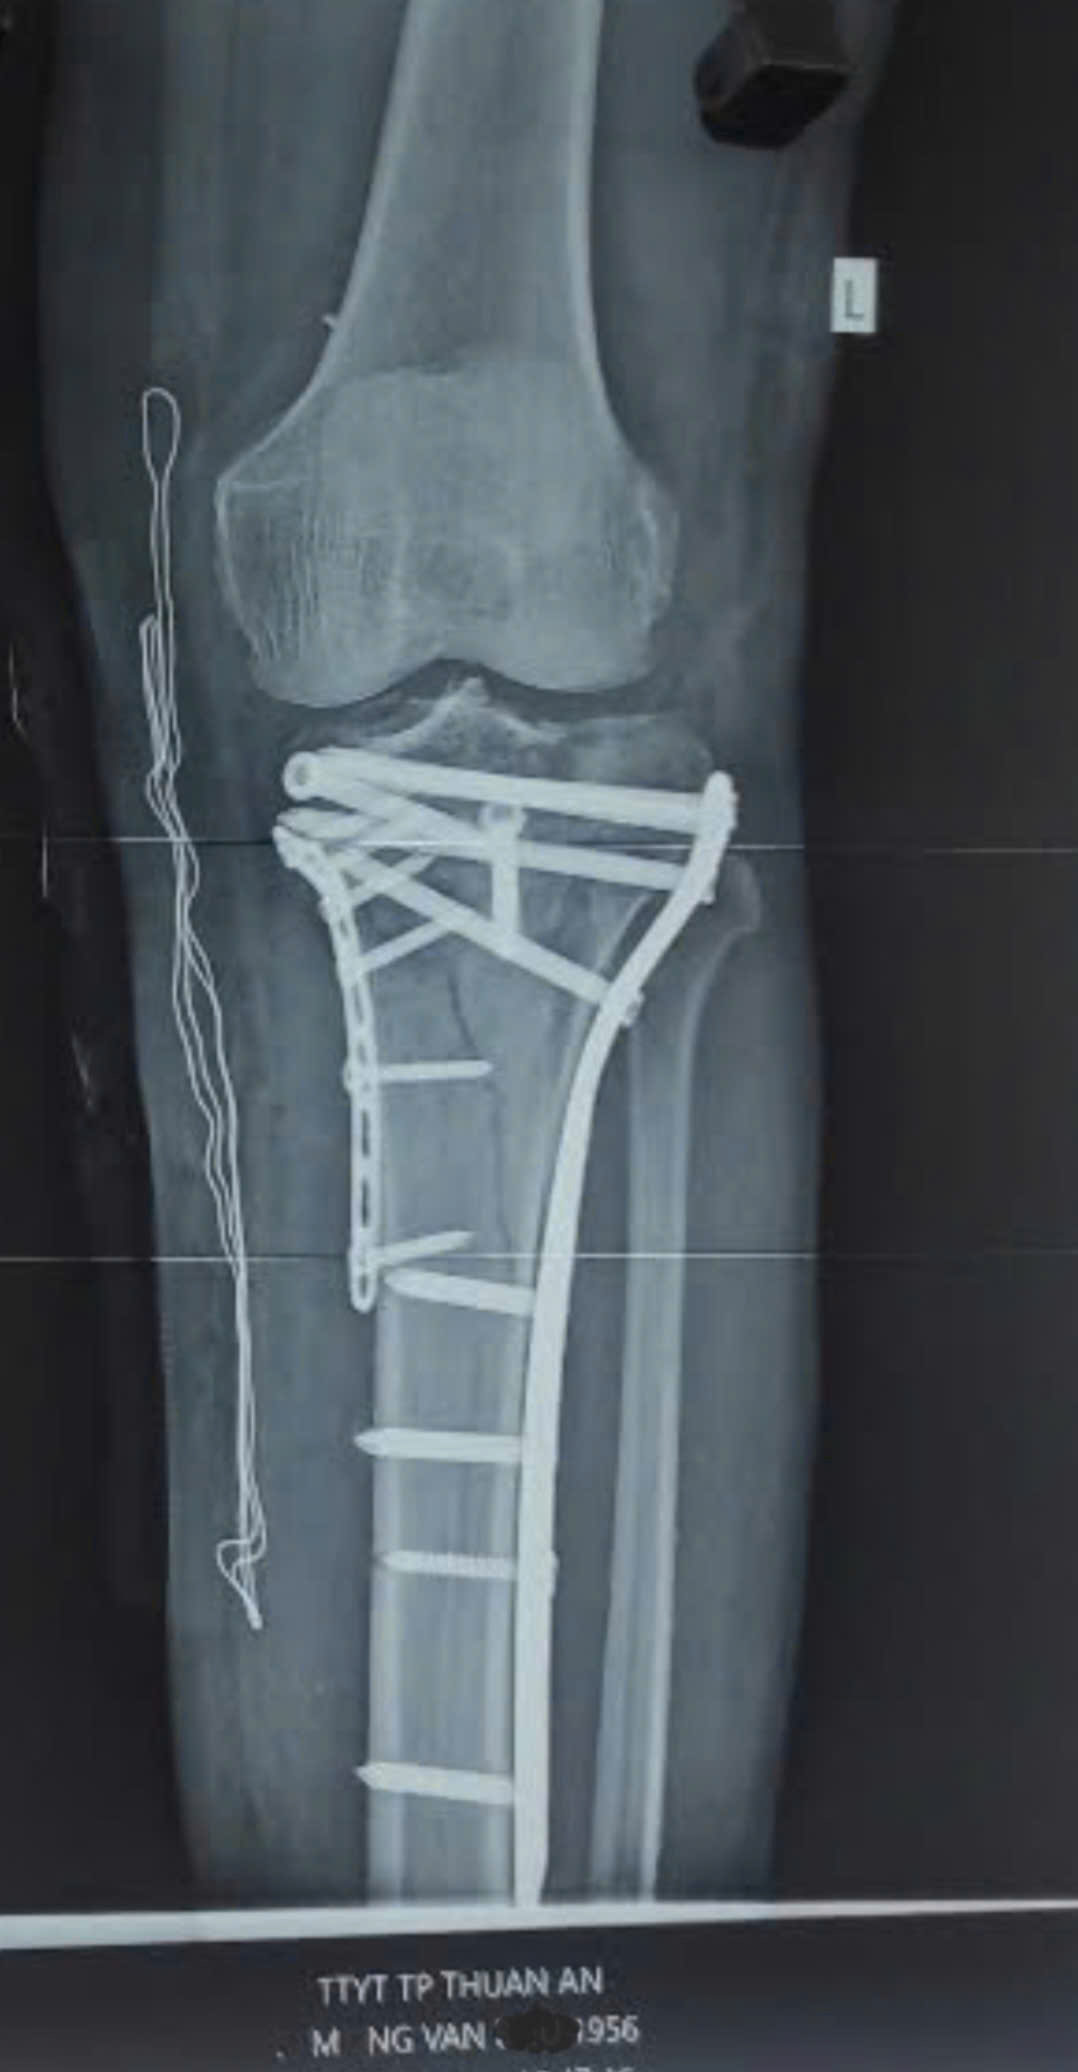

Các bác sĩ Trung tâm Y tế Khu vực Thuận An vừa qua đã phẫu thuật thành công và đạt kết quả rất tốt cho 1 ca chấn thương nặng khi chơi Pickleball với chẩn đoán gãy xương mâm chày phức tạp và các tổn thương khớp gối nghiêm trọng khác. Giúp bệnh nhân hồi phục vận động sớm và tránh để lại biến chứng lâu dài. Qua đây các bác sĩ tại Trung tâm Y tế Khu vực Thuận An cũng khuyến cáo rằng.

Phẫu thuật chỉ đặt ra khi tổn thương nặng, điều trị bảo tồn không hiệu quả